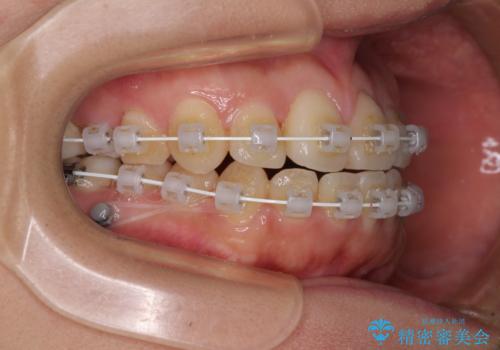

- 審美装置

受け口傾向の非抜歯矯正であったため、インビザラインによる矯正治療をお勧めしましたが、自己管理が面倒であるとのことで、ワイヤー装置にて行うこととしました。

右奥の歯が180度回転していることで、噛む度にワイヤーに無理な力がかかったようで、頻繁にワイヤーが切れてしまいました。また、下顎を後方に移動させるためのアンカースクリューも脱離することが多く、治療期間が長くなってしまいました。

ワイヤー矯正の注意事項(リスク・副作用など)